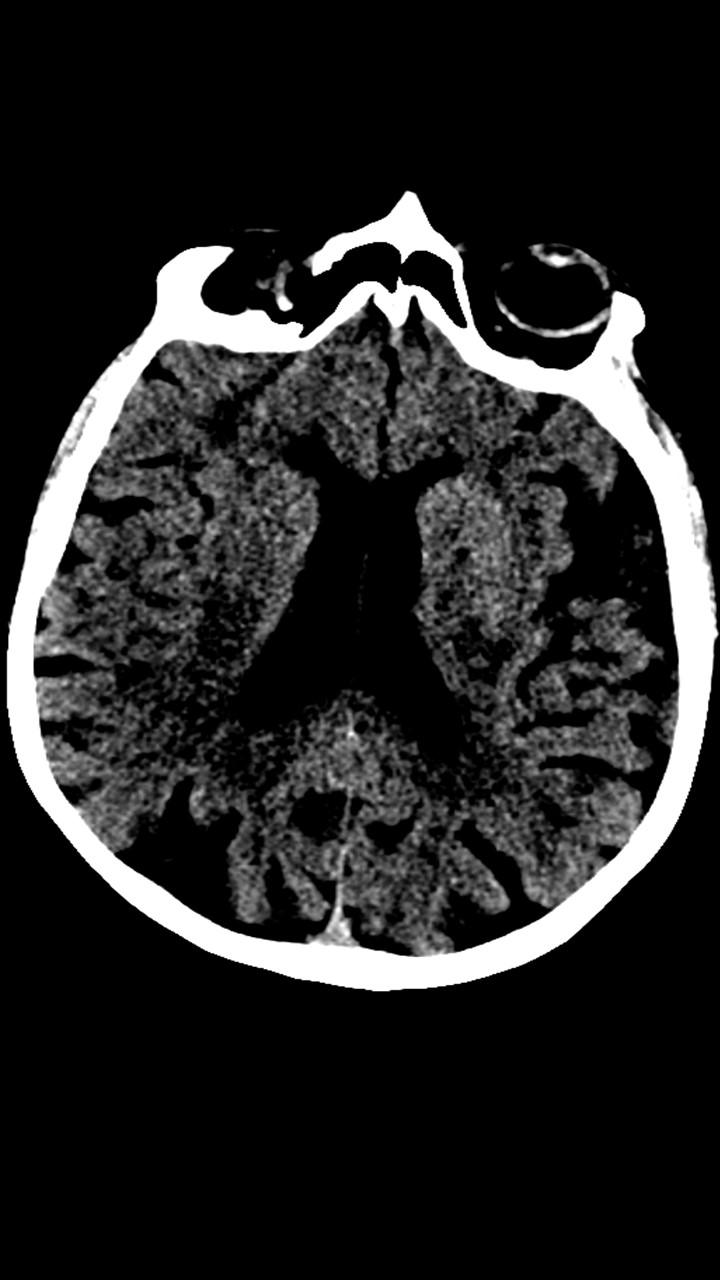

Hallazgos de TC de craneo:

• Cambios de leucoaraiosis periventricular.

• Hay zonas de hipodensidad subcortical fronto-parietal superior predominantemente izquierdas, de aspecto inespecíficos.

• Los halazgos son inespecificos, ante la ausencia de patología hemorragica aguda se decide continuar con el protocolo habitual.